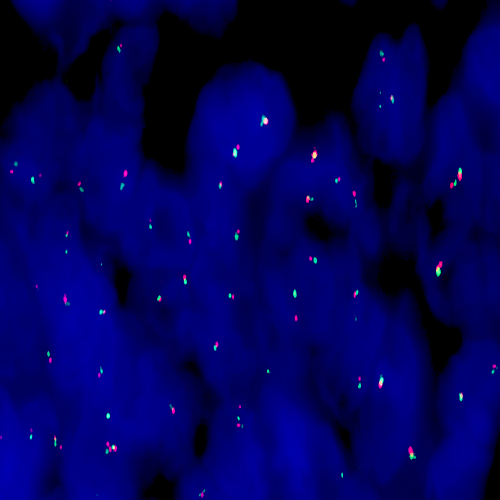

Squamous cell carcinoma of lung: Immunohistochemistry staining of p40. p40: clone BC28

p40 (Delta Np63) is a truncated product of p63. It is normally expressed in the basal or progenitor cell layer of stratified epithelia, basal cells of prostate, as well as myoepithelial cells of breast and salivary glands, and cytotrophoblasts in placenta, and shows a nuclear staining pattern with IHC. Among the numerous neoplasms positive for p40, squamous cell carcinomas of pulmonary and non-pulmonary origin can be identified from other malignancies.